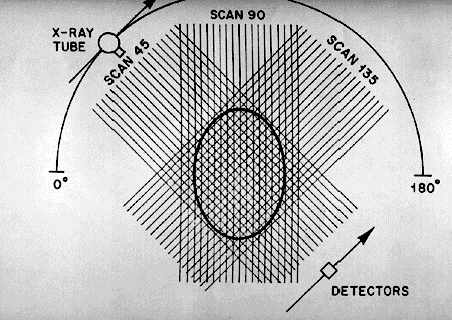

TERCERA GENERACIÓN 1976

• Rotación, Rotación

• 300-500 detectores

• Haz de RX cubre el ancho de la exploración

• Adquisición 2-10 Seg.